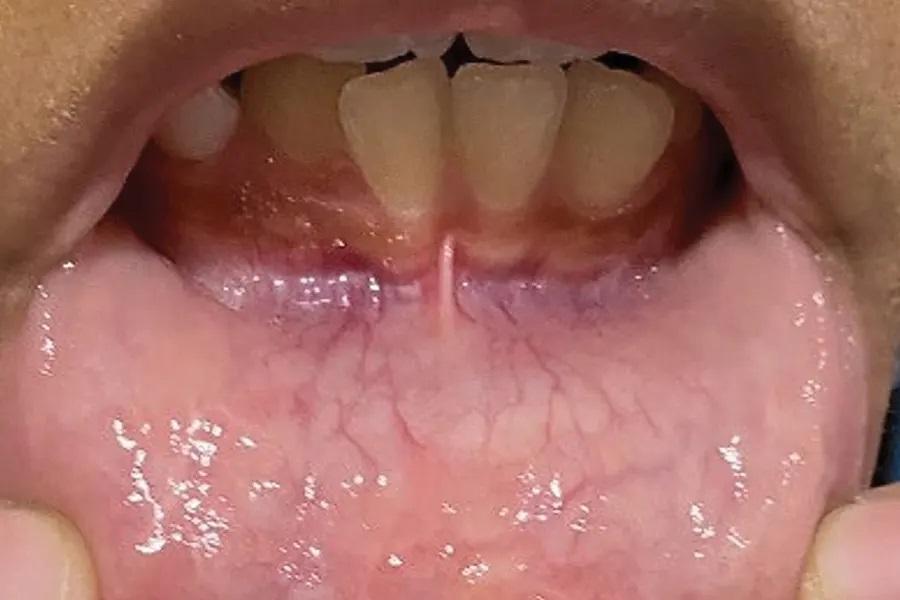

Настоящий клинический случай необычен по двум причинам. Во-первых, у пациентки было три образования на нижней губе, выглядевших как узелковые, по цвету слизистой, поражения, клинически соответствующие мукоцеле или фиброме раздражения (Фото 1). Поиск в литературе с использованием PubMed и Ovid Medline подтвердил редкость наблюдения: обнаружен лишь один описанный случай множественных мукоцеле. Во-вторых, все три образования были плотными при пальпации и проявляли признаки гиперкератоза, что затрудняло дифференциацию мукоцеле и фибромы раздражения без гистологической верификации (биопсии).

Фото 1. Первичное обращение: множественные поражения слизистой на внутренней поверхности нижней губы диаметром от 3 до 7 мм. Все три образования демонстрировали клинические признаки умеренного гиперкератоза.

Пациентка, афроамериканка 9 лет, направлена в отделение детской стоматологии Стоматологической школы UMKC из частной практики с жалобой на «шишки на нижней губе». Затем пациентку направили в клинику продвинутой подготовки по пародонтологии этой же школы для обследования и биопсии. Имелись три образования, идентичные по клинической картине, отличались лишь размерами. Срок их существования составлял 2,5 месяца. Пациента охотно сотрудничала с врачом, и с ее слов образования увеличиваются, когда она их кусают, и сильно ее раздражают. При клиническом осмотре выявлены три поражения слизистой на внутренней поверхности нижней губы диаметром приблизительно 7 мм, 5 мм и 3 мм. Все три образования демонстрировали клинические признаки гиперкератоза и были плотными при пальпации (Фото 1).